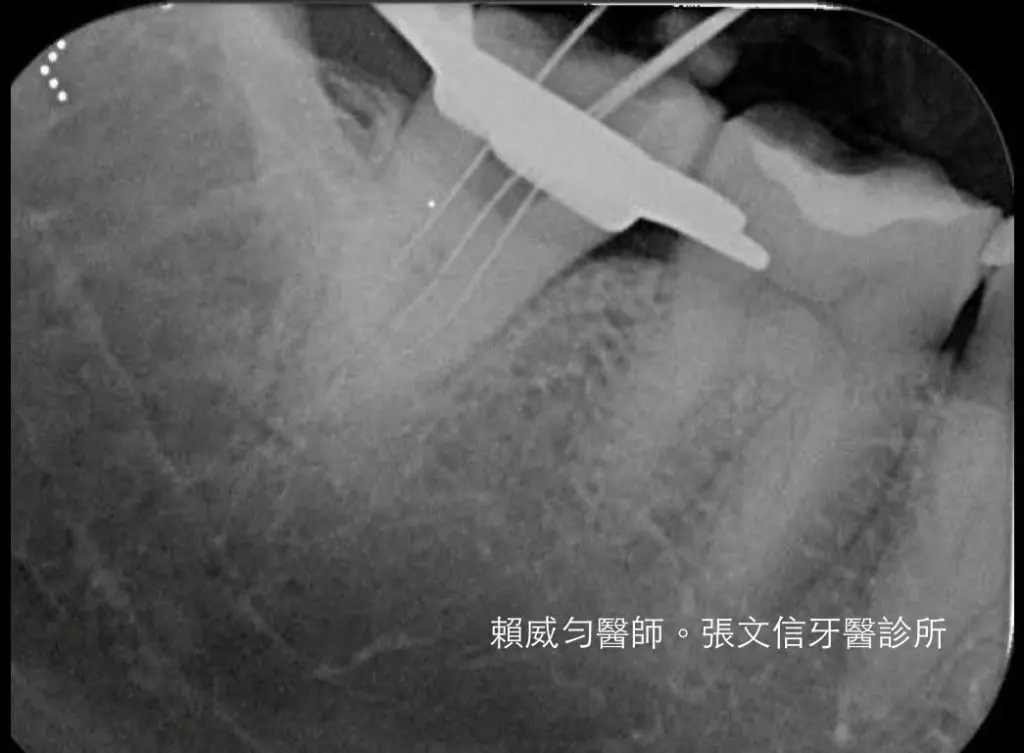

C-形根管的開口多變,X光片的特徵容易讓人混淆,根管內部結構複雜,死角眾多。

一打開牙齒,根管邊界無法辨認,全部都連成一氣。醫師從哪個方位入手都不對。插了根管銼針,X光裡,銼針是直直地從正中央貫穿牙齒,看了都讓人膽戰心驚。